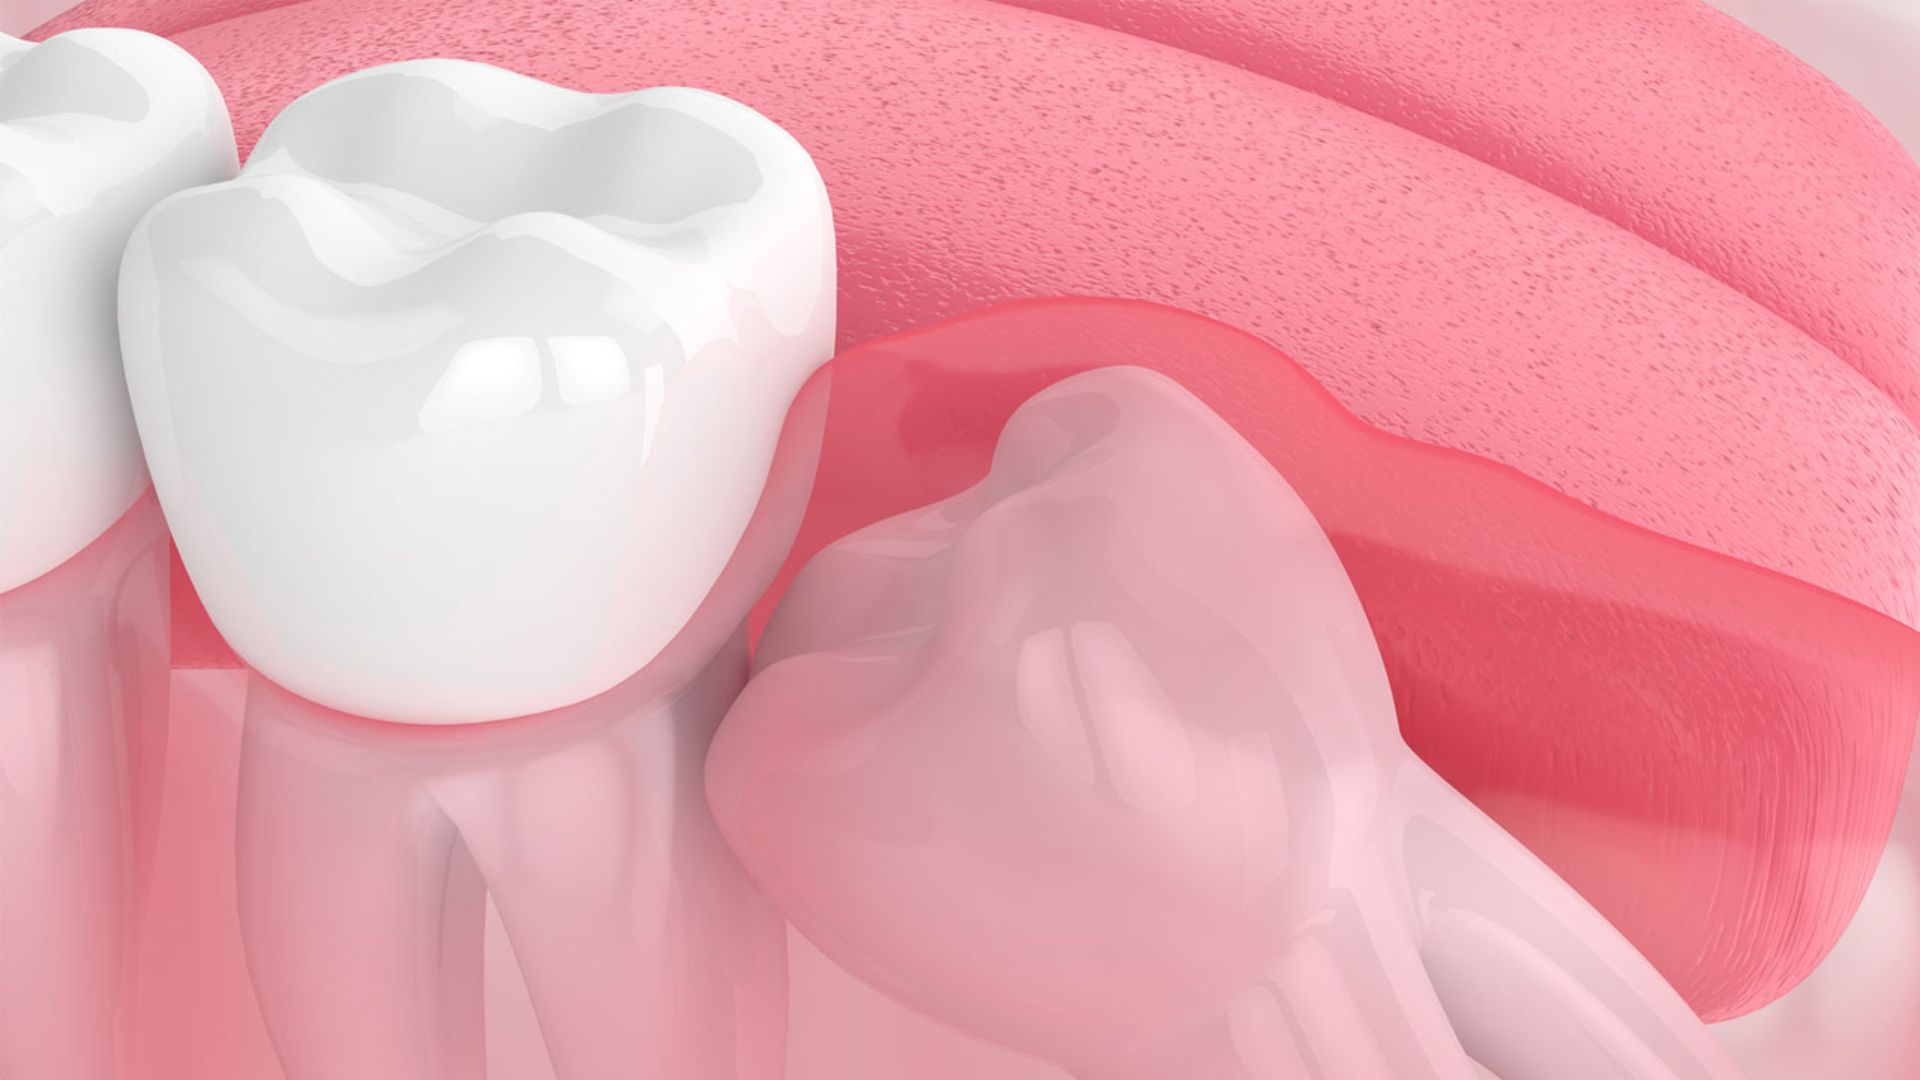

Răng khôn là những chiếc răng mọc phía trong cùng hai hàm răng, trường hợp xương hàm của chúng ta đã ngừng phát triển. Răng khôn thường mọc từ giai đoạn tuổi 17 đến 25, dù vậy cũng có một số trường hợp răng khôn mọc ngoài giai đoạn này. Sẽ có tổng cộng 4 chiếc răng khôn ở mỗi người chúng ta ở cả 2 hàm.

Vì răng khôn mọc khá sát vách và trong cùng một hàm dễ dẫn đến tình trạng mọc đâm xiên, mọc lệch vào răng bên cạnh dẫn đến hiện tượng sưng lợi, đau răng, nhiễm trùng vùng nướu xung quanh. Bên cạnh đó, răng khôn thường sẽ được nhổ bỏ vì thực tế chẳng có công dụng gì nỗi bật.